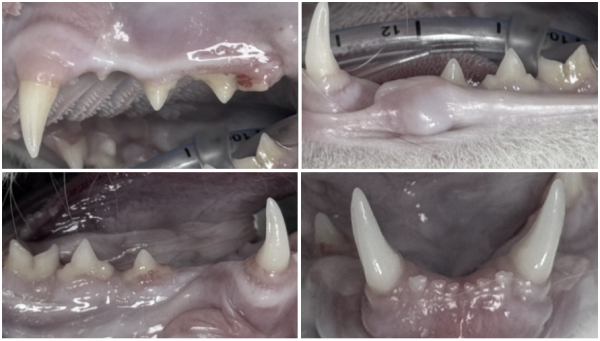

삼동이(가명)는 건강검진과 치과 검진을 위해 내원한 고양이입니다.

기본 검사에서는 감기 증상 외에는 특별한 이상이 없었고,

마취 후 구강 검사를 진행했습니다.

검진 과정에서 우측 송곳니가 반대쪽보다 짧아져 있는 모습이 확인되었습니다.

아래쪽에서 빨간 구멍처럼 보이는 노출된 치수관이 발견되었습니다.

이 치아 상태는 치아 파절로 인해 신경이 노출된 상태이며,

이 구멍을 통해 세균이 치아 내부로 침투하고 있다는 의미입니다.

이는 고양이 송곳니 부러짐에서 흔히 발생하는 합병증 중 하나입니다.

신경관 길이를 측정

Niti file로 근관을 넓힘

gutta percha, MTA 충전

레진으로 마무리